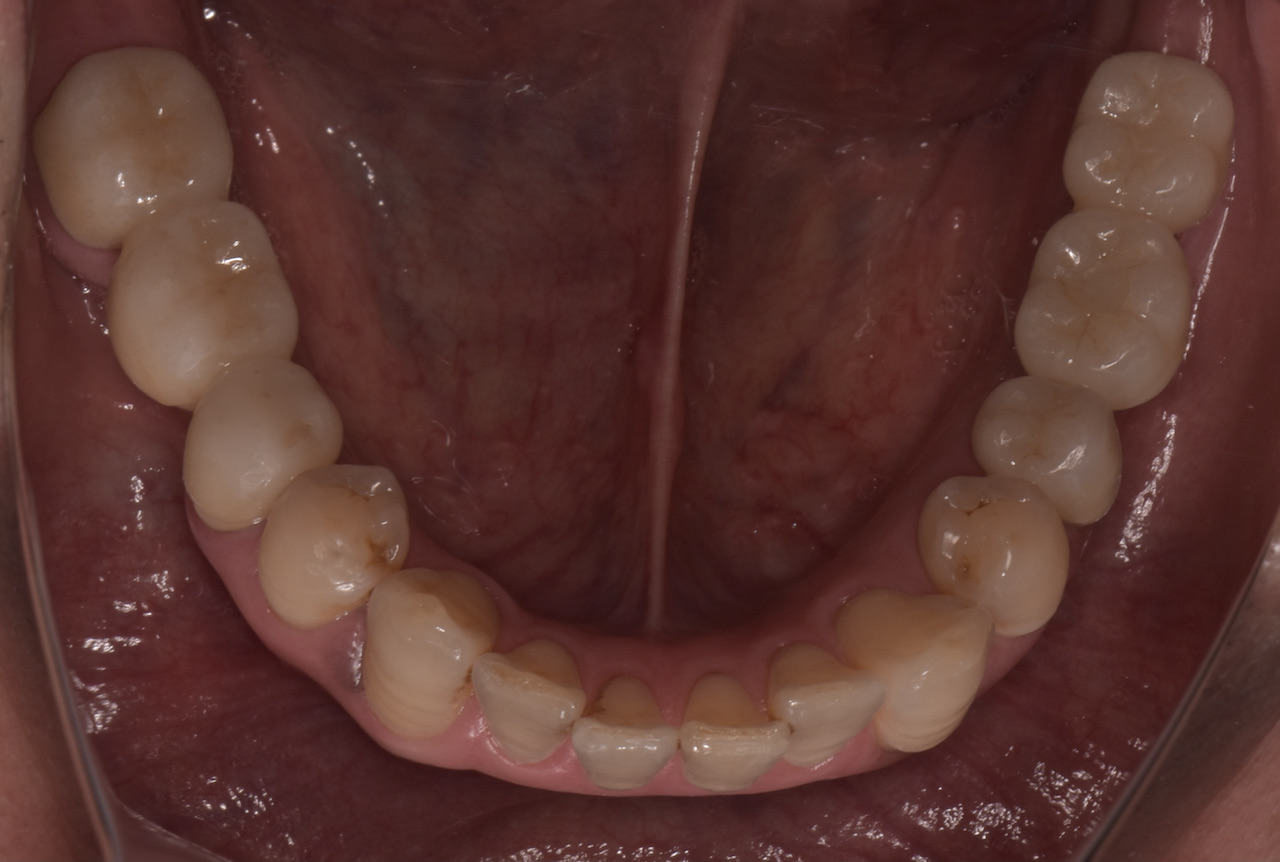

全顎的に複数の治療部位で、インプラント・ブリッジ・ダイレクトボンディング・セラミッククラウンなど、適切な治療方法を組み合わせて包括的な治療を進めました。

治療を終えた「T-scan」による咬合調整後の患者さんの感想を伺うと「とても良く咬め、インプラントが入っていても全く違和感を感じない」という事でした。このようにデジタルで計測される客観的なデータと患者さんこそが一番感じるご自身からの体の声を一体化させる治療が大切です。

この「T-scan」はインプラント治療にも応用できる点が他の計測装置との違いの一つです。「I-24」と表示されているのはインプラントが埋入されている表記で、そこに他の歯と同じ力が掛かっている事を示しています。これは通常のリボン紙(咬合紙)では全くわかりません。このように天然歯、補綴歯、インプラント治療歯の力の違いを把握すれば、インプラントに掛かる力による治療後のトラブルを回避出来ると考えます。